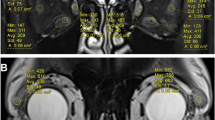

For further exploration of the correlation between clinical severity assessment and PET parameter, we performed linear regressions: On the early static images, a statistically significant correlation between NOSPECS and TLG (summed TLG: R2 = 0.53, p = 0.003) and between NOSPECS and MTV (summed MTV: R2 = 0.49, p = 0.006) was observed. Similarly, a statistically significant correlation between TLG (summed TLG: R2 = 0.61, p = 0.001) and MTV was observed (summed MTV: R2 = 0.52, p = 0.004) on the late static images (Fig. 6).

Detailed muscle analysis

To further explore the muscle inflammation, each rectus muscle was evaluated separately for each eye in PET and MRI images. We observed a statistically significant correlation between the rectus medial muscle diameter on the one hand and SUVmax, and TLG derived from the early static images on the other hand (R2 = 0.25–0.26, p < 0.01). In late static images, only TLG showed a significant correlation (R2 = 0.38, p < 0.001, Fig. 7). The diameter of the inferior rectus muscle was also significantly correlated with SUVmax, SUVmean, MTV, and TLG derived from the early static images (R2 = 0.29–0.41, p > 0.001). Similarly, late static images showed only a significant correlation with TLG (R2 = 0.55, p < 0.0001). No statistically significant correlation was observed between the superior and lateral rectus muscles and PET parameters in early and late static images.

As assessed by Pearson’s correlation coefficient, no significant correlations between the PET parameters obtained from IEMS on the one hand, and motility of the inferior (p = 0.21–0.95), lateral (p = 0.29–0.75), medial (p = 0.07–1.0), and superior (p = 0.20–0.67) rectus muscles were observed.

Regarding the severity and eye muscle involvement, group comparison showed that patients with sight-threatening GO had significant higher TLG compared to mild and moderate to severe (median 30.9 vs. 8.3/9.9, p = 0.03). Mild and moderate-to-severe patients showed similar muscle activity in PET.